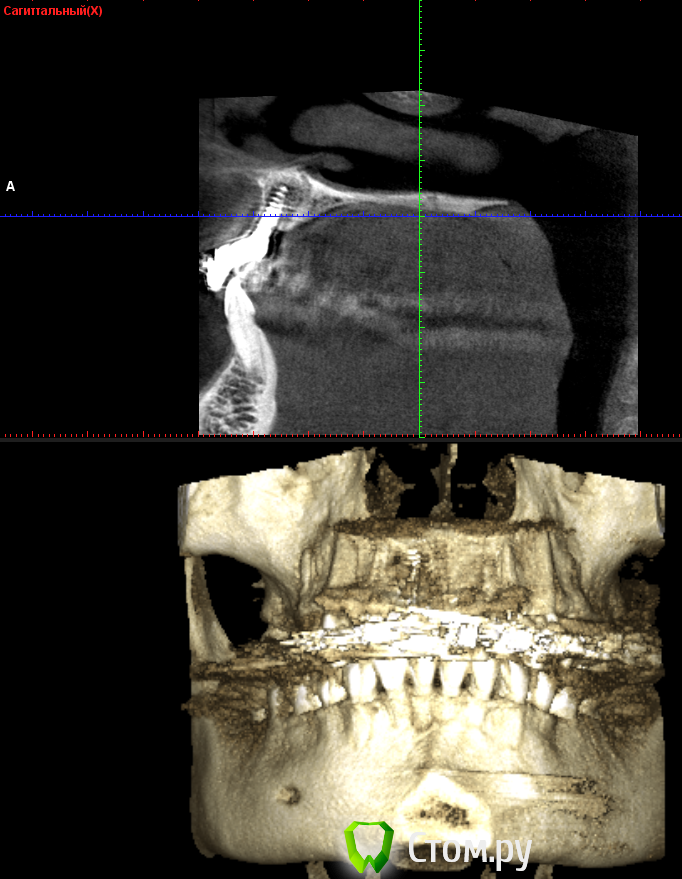

***Irene*** Опубликовано 22 октября, 2014 Поделиться Опубликовано 22 октября, 2014 (изменено) Уважаемые знатоки!Сделали КТ верхней челюсти с имплантом, потому что коронку ну никак не вместить по человечески, десна ходуном ходит, и увидели такую картину (см картинки). То, что имплант стоит слишком глубоко в нёбо и не в зубном ряду - видно даже невооруженным и непрофессиональным взглядом, шейка коронки, как видно на снимке, под большим углом, но коронка все равно торчит вперед.В общем, вердикт доктора - удалять и ставить новый с предварительной аугментацией. Сразу скажу, что в клинике, в которой ставили, клялись, что это нормально, но я оттуда сбежала, вердикт уже из новой клиники.Вопросы:1) На самом ли деле имплант стоит в кости криво?2) Не опасно ли удаление прижившегося импланта и какие могут быть последствия?3) Какова последовательность в данном случае: удаление+аугментация, затем новая имплантация через полгода, затем коронка через полгода? Изменено 22 октября, 2014 пользователем ***Irene*** Ссылка на комментарий

***Irene*** Опубликовано 23 октября, 2014 Автор Поделиться Опубликовано 23 октября, 2014 Ну, в общем-то, внутри рта это выглядит именно так, как на 3 КТ - смещение из зубного ряда, причем, нормальное такое. Врач говорит, что это из-за того, что на КТ 4 недостаток кости с внешней стороны и что процесс будет усугубляться, поэтому нужно нарастить кость, удалив этот имплант, и вставить новый. Фиг с ней, с кривизной, больше волнует вопрос, на самом ли деле там спереди не хватает кости и она может "уйти" окончательно, из-за чего имплант вывалится сам? И не развезет ли мне всю челюсть удалением импланта (ведь он же врос в кость), что потом всякие косметические операции понадобятся и пр. Ссылка на комментарий